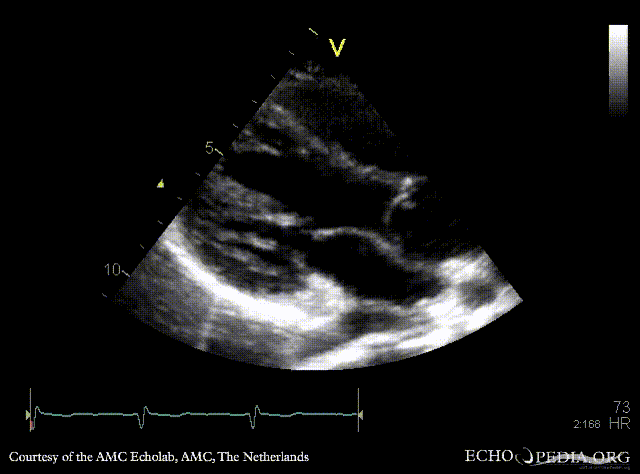

Abnormal pulmonary vein drainage

PLAX: dilated coronary sinus PLAX with Color Doppler: pulmonary vein drainage into coronary sinus, connection with left atrium